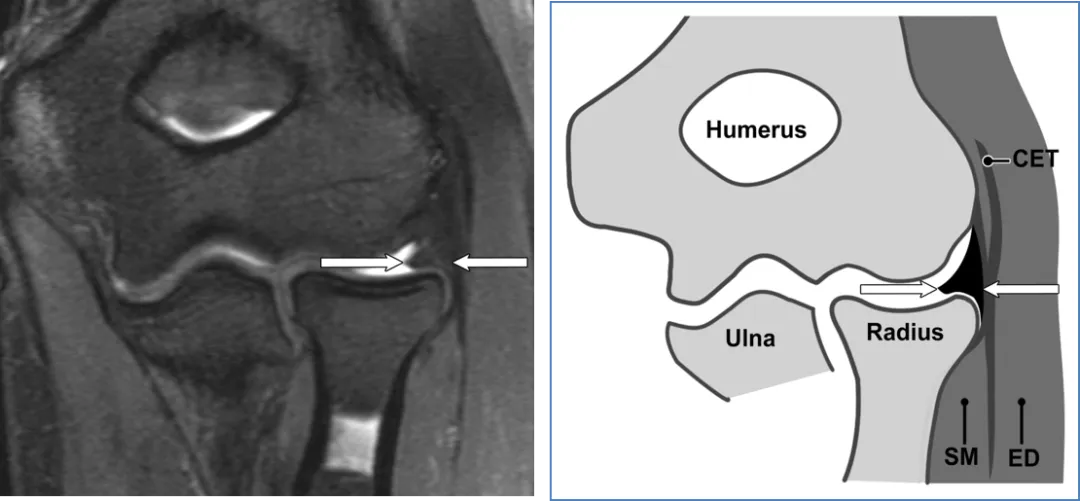

RCL。(a)28岁男性的冠状STIR磁共振成像。RCL外观均匀(箭头)。(b) RCL对应示意图(箭头)。SM = 旋后肌。

外侧尺侧副韧带(LUCL)

(a)27岁女性的冠状STIR磁共振成像。外侧尺侧副韧带近端(白色箭头)和远端(黑色箭头)信号强度正常。(b) 对应的外侧尺侧副韧带示意图显示了近端(白色箭头)和远端(黑色箭头)两个方面。CET = 伸肌总腱。